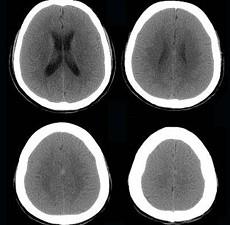

问题 男,57岁,头痛、头晕1周,言语不清,饮水呛咳两天,既往有鼻咽癌病史,给予放射治疗,CT检查如图所示,最可能的诊断为()

选项 A.脱髓鞘病变 B.脑炎 C.放射性脑病 D.脑梗死 E.胶质瘤

答案 C